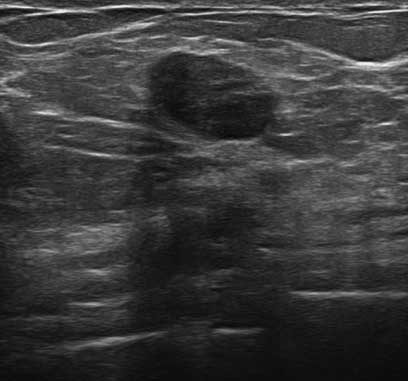

The target dataset was developed from 35 breast ultrasound scans that were segmented by an image-processing expert with extensive experience in breast lesion segmentation (the second author). The images, collected from the Web, are of different dimensions, ranging from to pixels (Figure 3, images resized for sake of illustration). These are the same images used to introduce EFIS originally [1].

Ultrasound images are generally difficult to segment, primarily due to the presence of speckle noise and low level of local contrast. It should be noted that the segmentation of ultrasound actually does require a complete processing chain, (including proper preprocessing and post-processing steps). However, the purpose of using these images was solely to demonstrate that the accuracy of the segmentation can be increased with the application of SC-EFIS.